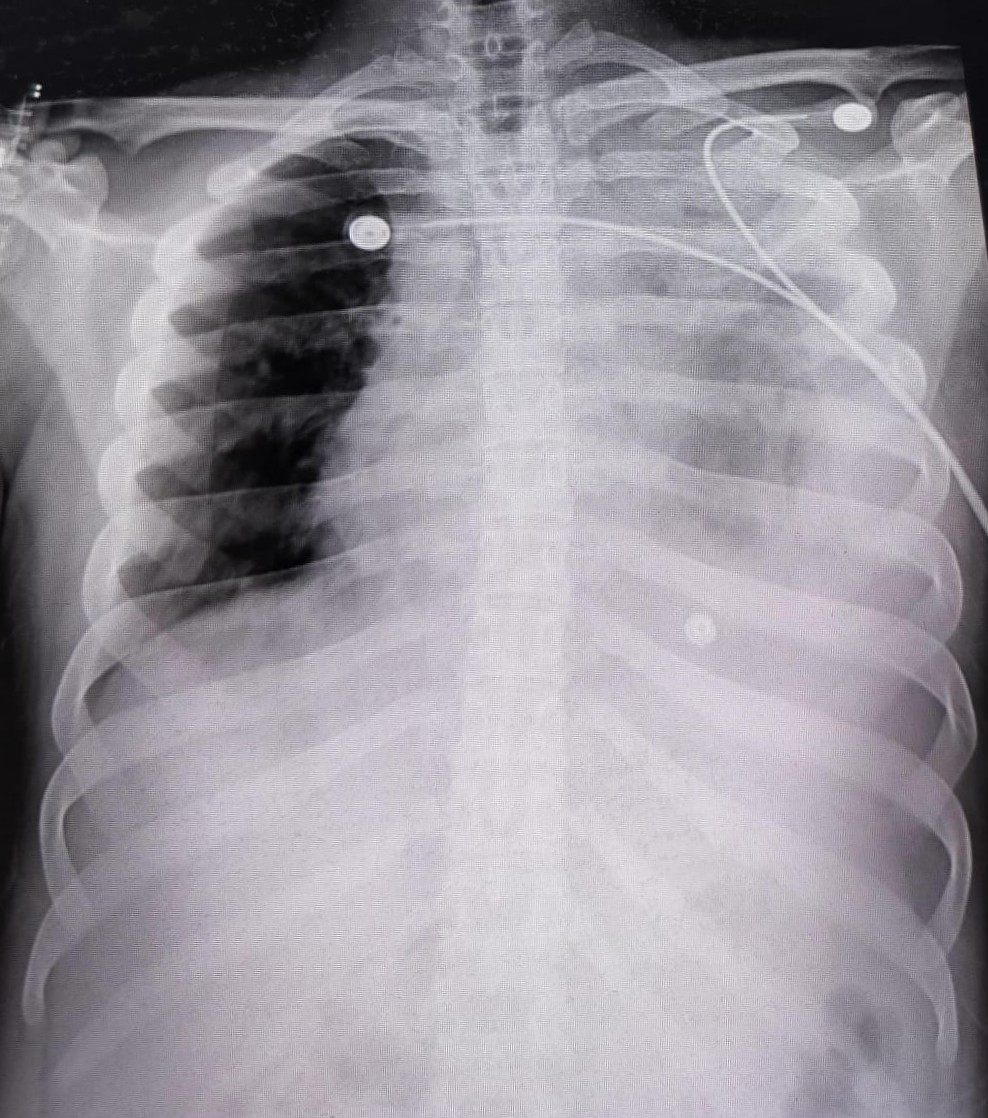

| 211 | IGGMC, Nagpur, Nagpur | P2 | 29-4261 | DHANRAJ HEDAU | Consent taken on Paper | 65 Yrs. |

Provisional Diag : Lung mass with ? Malignancy

Final Diag : Lt lung mass with malignancy (T1 N1 M1) with pneumothorax |

Result awaited (Suspected TB/Non-TB) | Abnormality visible on x-ray |

View |